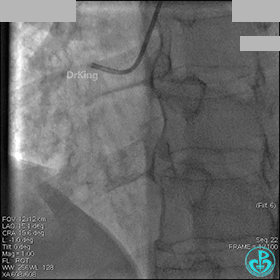

右冠脉血流3级,患者无症状,终止手术。

术后患者无特殊不适。

1周后再次上台,右冠脉3级血流,3段局限性严重狭窄,内膜模糊,应该是上次操作夹层遗留下的血肿。